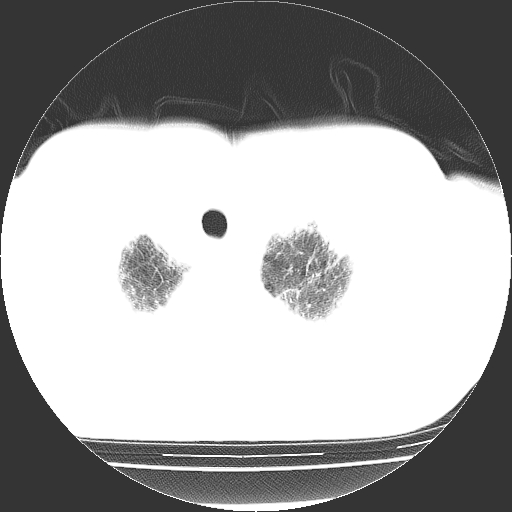

男,68岁,咳嗽、胸闷、发烧三天,查体:双肺散在湿罗音。

首先考虑特发型肺间质纤维化;两侧少量胸腔积液。

依据:1、两肺广泛条索状、网格状、蜂窝状改变。

1.双肺间质纤维化并感染;

2.双肺慢支炎肺气肿;

3.支扩并感染;

4.肺原性心脏病;

5.双侧胸腔少量积液;双侧胸膜增厚。

双肺多发条索状、网格状及小灶状密度增高影。考虑慢支合并感染.间质纤维化,双侧少量胸腔积液

两肺广泛条索状、网格状、蜂窝状改变。肺间质纤维化,肺心病,双侧胸腔积液